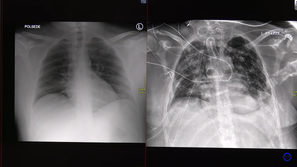

UKC Ljubljana Video: Strašljive posledice, ki jih povzroči covid-19 Dva primera covid pljučnice - pri enem bolniku se je stanje relativno hitro izboljšalo, drugemu, le 30-letnemu bolniku,…